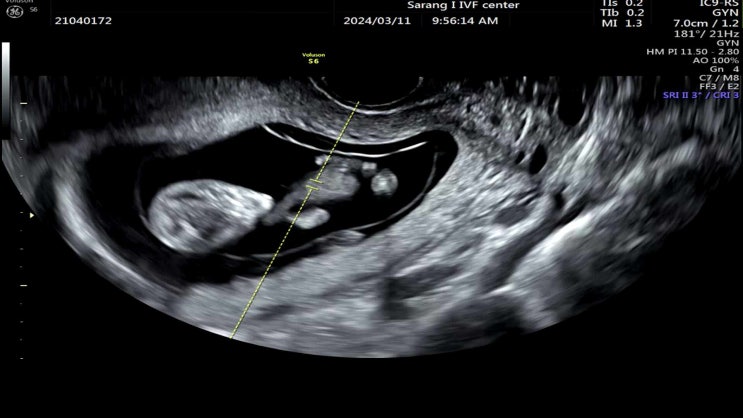

[11주 1일] 바라고 바라던 예비 자매맘이 되다!

드디어 11주 1일 사랑아이 여성의원 졸업날이 왔다. 주사 끊고, 질정 끊고 그래도 잘 커준 두찌 첫째인 구...